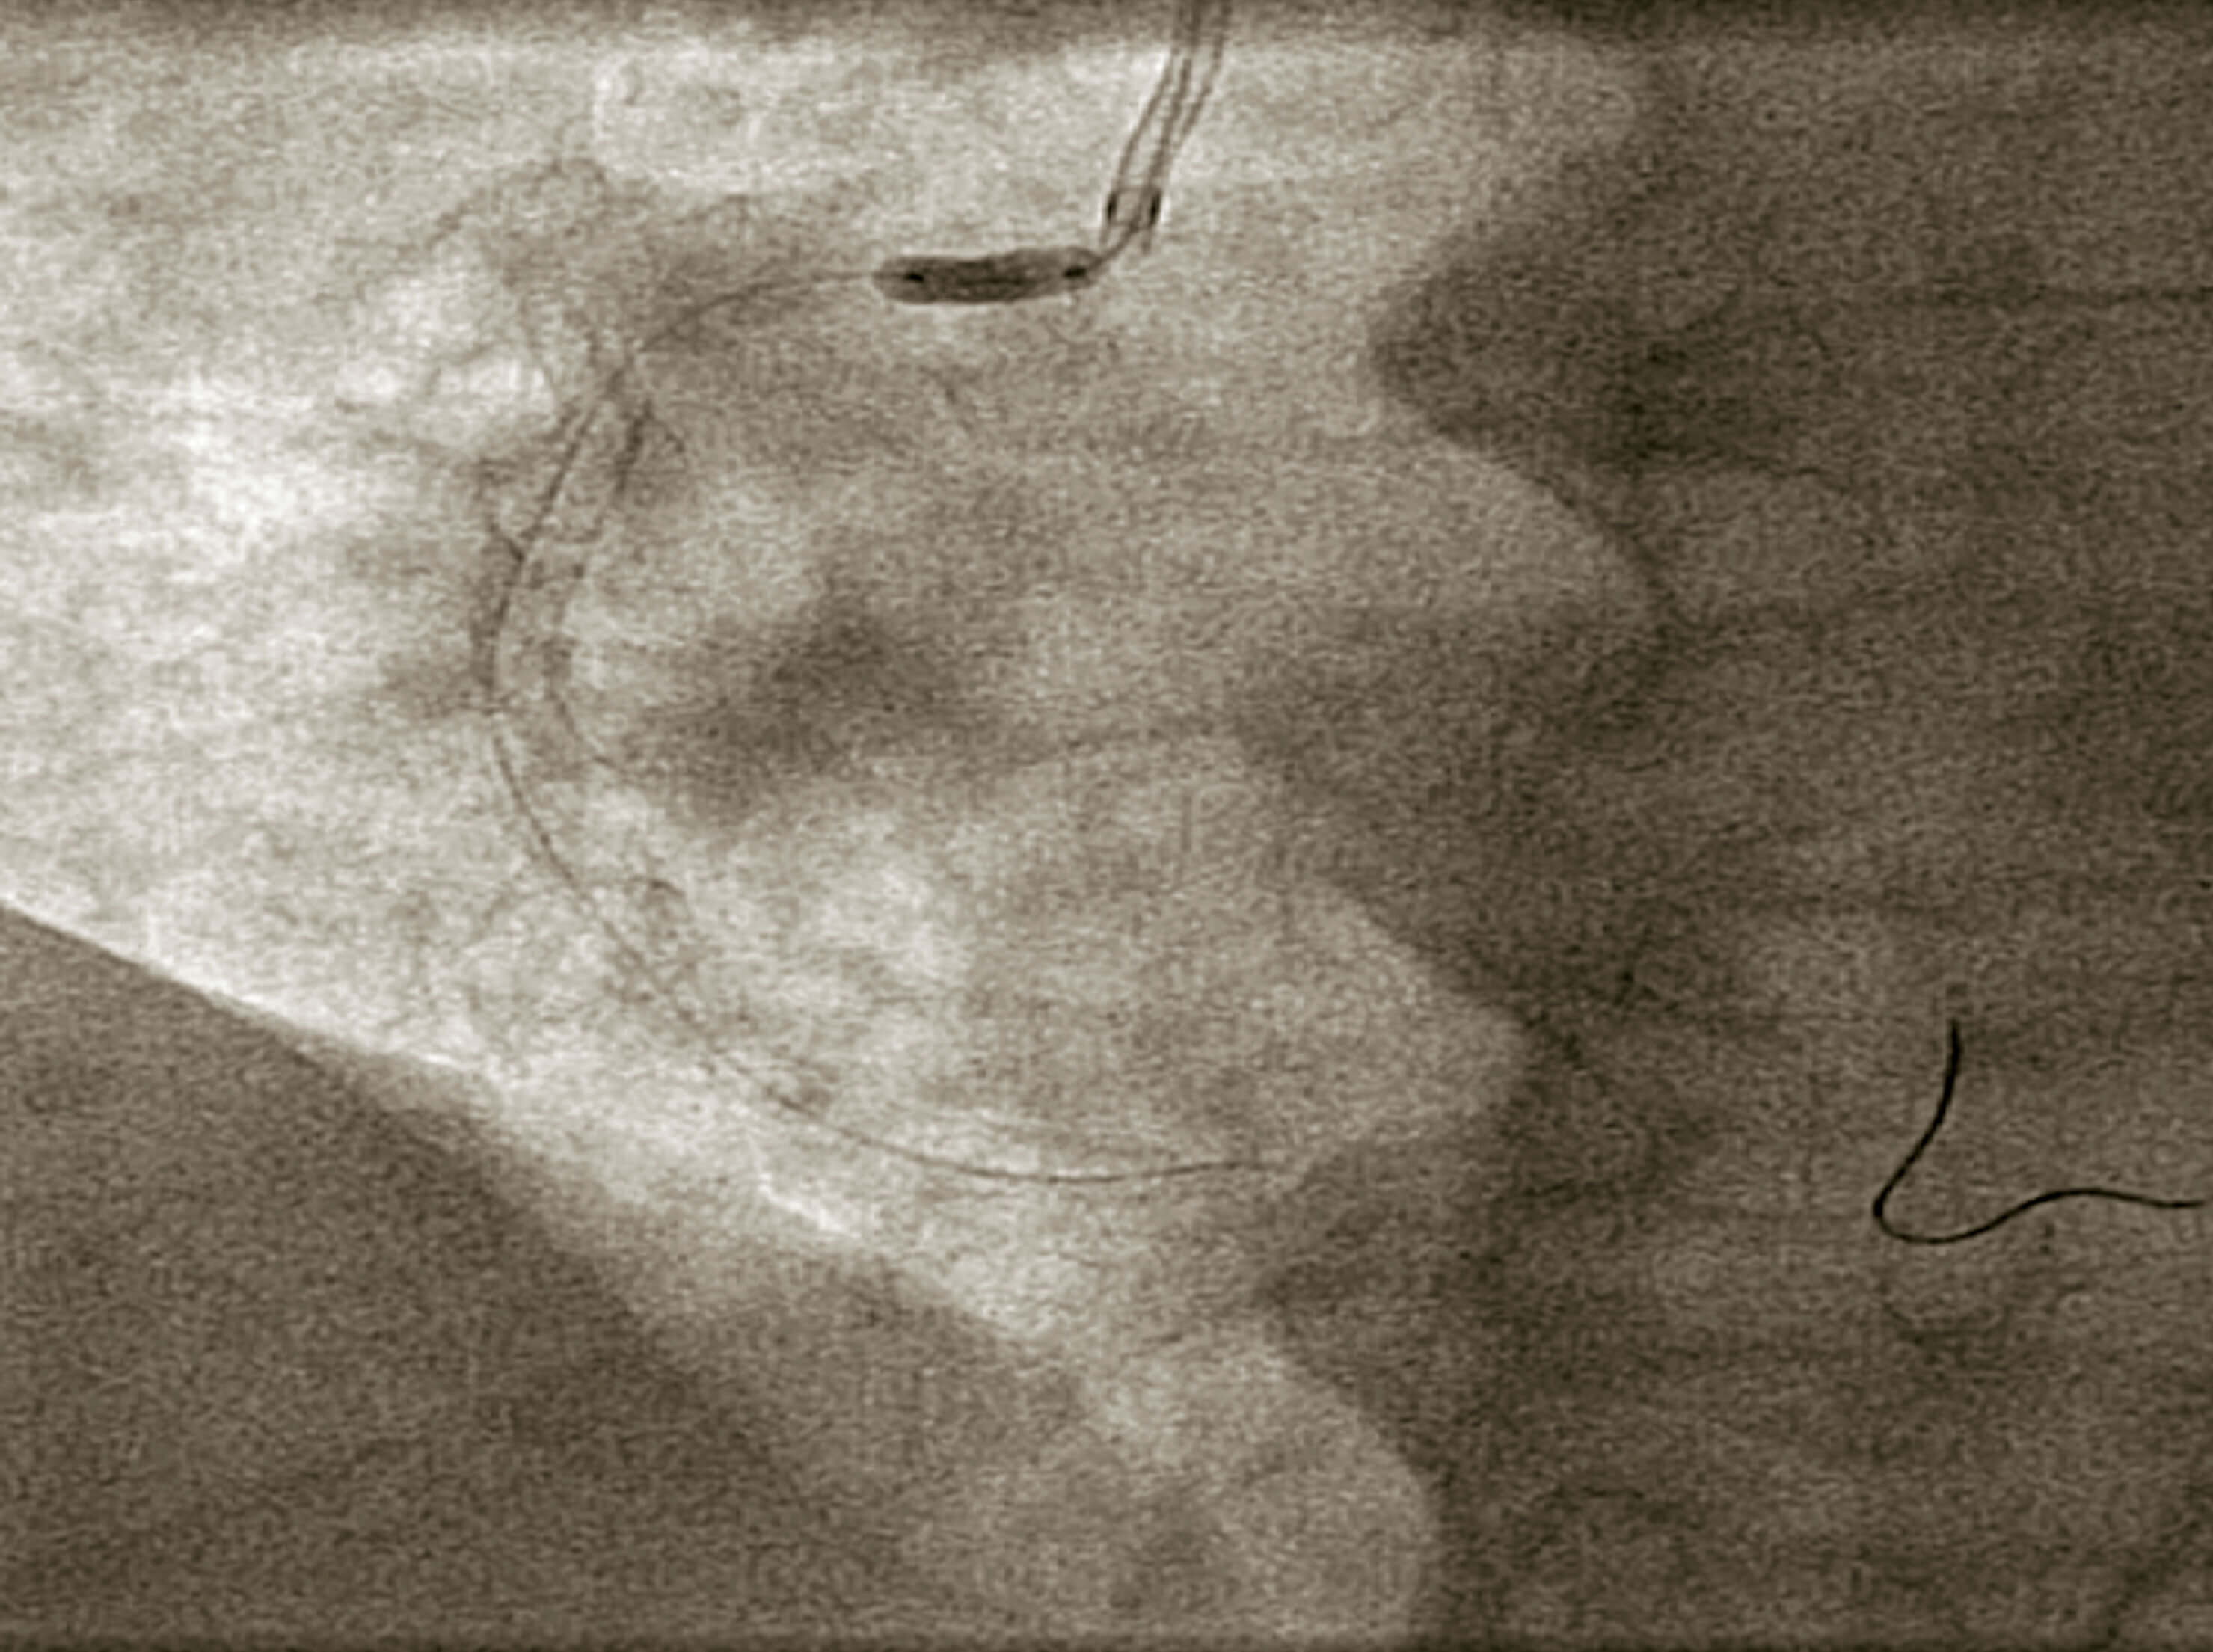

Se procedió a cambio a catéter guía JR de 6 Fr y se pasó una guía de angioplastia Sion (Asahi). Se realizó predilatación con balón no distensible de 3,5 × 10 mm (figura 2) y se eligió un stent liberador de sirolimus Orsiro de 3,5 × 18 mm, cubriendo el ostium (figura 3).

Figura 2. Predilatación con balón no distensible de 3,5 × 18 mm a 14 atm, con adecuada apertura.